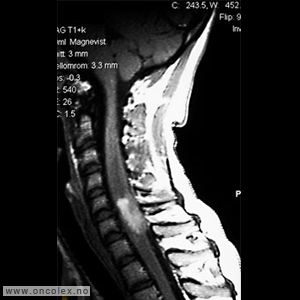

Bildediagnostiske undersøkelser

MR er det viktigste diagnostiske hjelpemiddel for å påvise svulst i ryggmargen, ryggmargsnervene og ryggmargshinnene. CT kan også brukes, men har klare begrensninger når det gjelder fremstilling av svulstene. Blant annet kan svulster som ikke tar opp kontrast bli oversett. CT og skjelettrøntgen kan imidlertid være nyttig for å kartlegge grad av skjelettødeleggelse og eventuell instabilitet i ryggsøylen.

Bildeeksempler